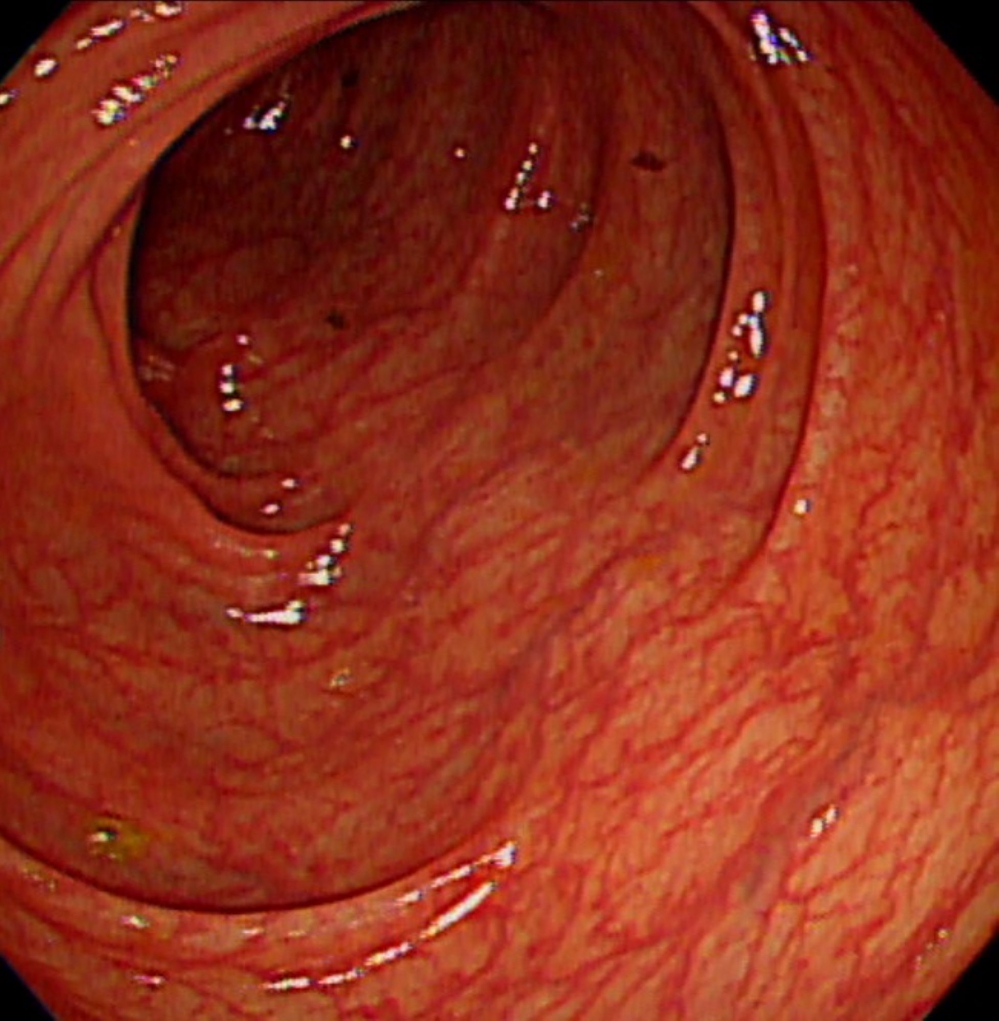

朱峻廷醫師指出,FAP是APC基因(腫瘤抑制基因)發生突變,目前最有效的預防方式是全大腸切除手術,保留直腸部分,配合定期檢查,患者仍能維持良好生活品質。此外,FAP患者不僅會形成大腸癌,此類病人罹患上腸胃道瘜肉與腫瘤、甲狀腺腫瘤,消化系統腫瘤及神經內分泌腫瘤的機率也較高,即使接受預防性全大腸切除手術後,仍需要定期追蹤胃、小腸以及甲狀腺,才能確保健康。